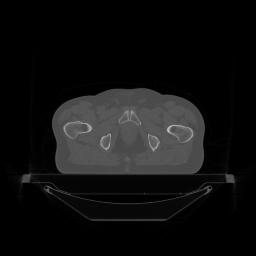

(a) Ground truth

Refer to caption

(b) PDFP, PSNR= 50.59

(c) SPDFP, PSNR= 40.27

(d) SVRG-PDFP, PSNR= 51.79

(e) OPG-ADMM, PSNR= 41.24

(f) SVRG-ADMM, PSNR= 51.75

Figure 8: Average of one slice of 3D image reconstruction of different method over 10 repetitions.

FIG. 6 give the results of PSNR of the images over time on two devices and FIG. 7 show the computation time for different algorithms to achieve a given PSNR level (if achievable). It can be seen that the stochastic algorithms are generally quicker than deterministic algorithms as the problem size of this example is much larger than 2D case. The stochastic algorithms with SVRG perform better with both GPU devices in terms of both time and accuracy. Finally, a slice of the reconstructed 3D images with different algorithms are shown in FIG. 8 to further verify the image quality of the reconstructed images of different algorithms.